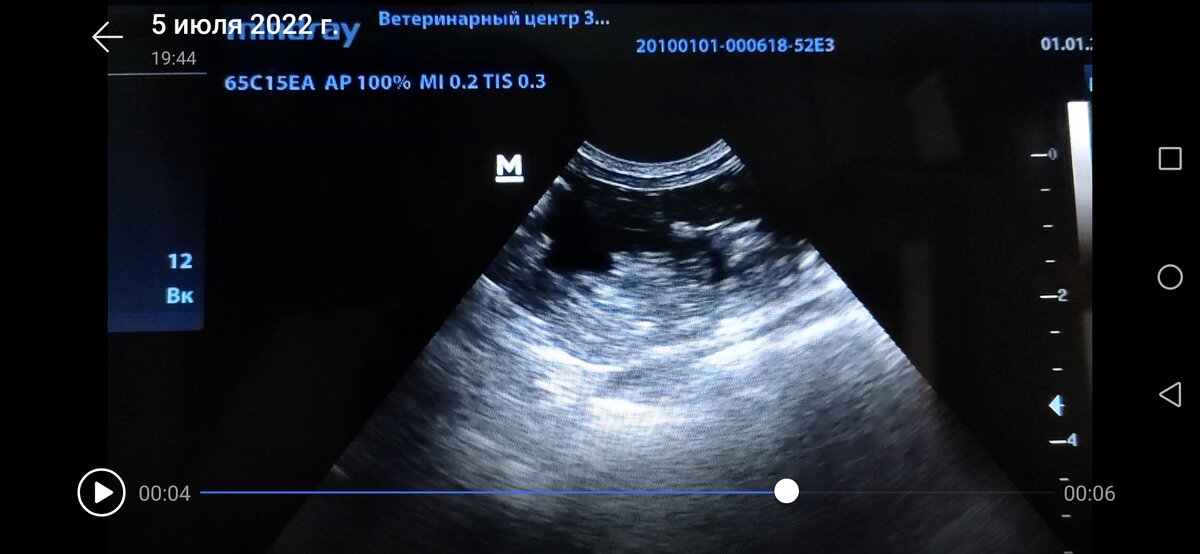

Проведено ультразвуковое исследование, которое показало интересные образования одинаковой ультразвуковой картины, но в разных местах. Одно крупное образование в проекции уретры, кажется, что даже в ее просвете, возможна частичная или полная обструкция. Размер около 2 см, с четко очерченной границей, тонкостенное образование, в полости которого видна жидкость, в на дне какое-то клеточное содержимое, движущееся при дыхании. Второе образование похожее на первое, но с дистальным усилением в области краниального полюса левой почки, возможно опухоль надпочечника. Третье образование в брюшной полости среди петель кишечника краниальнее мочевого пузыря с той же картиной и с теми же характеристиками.